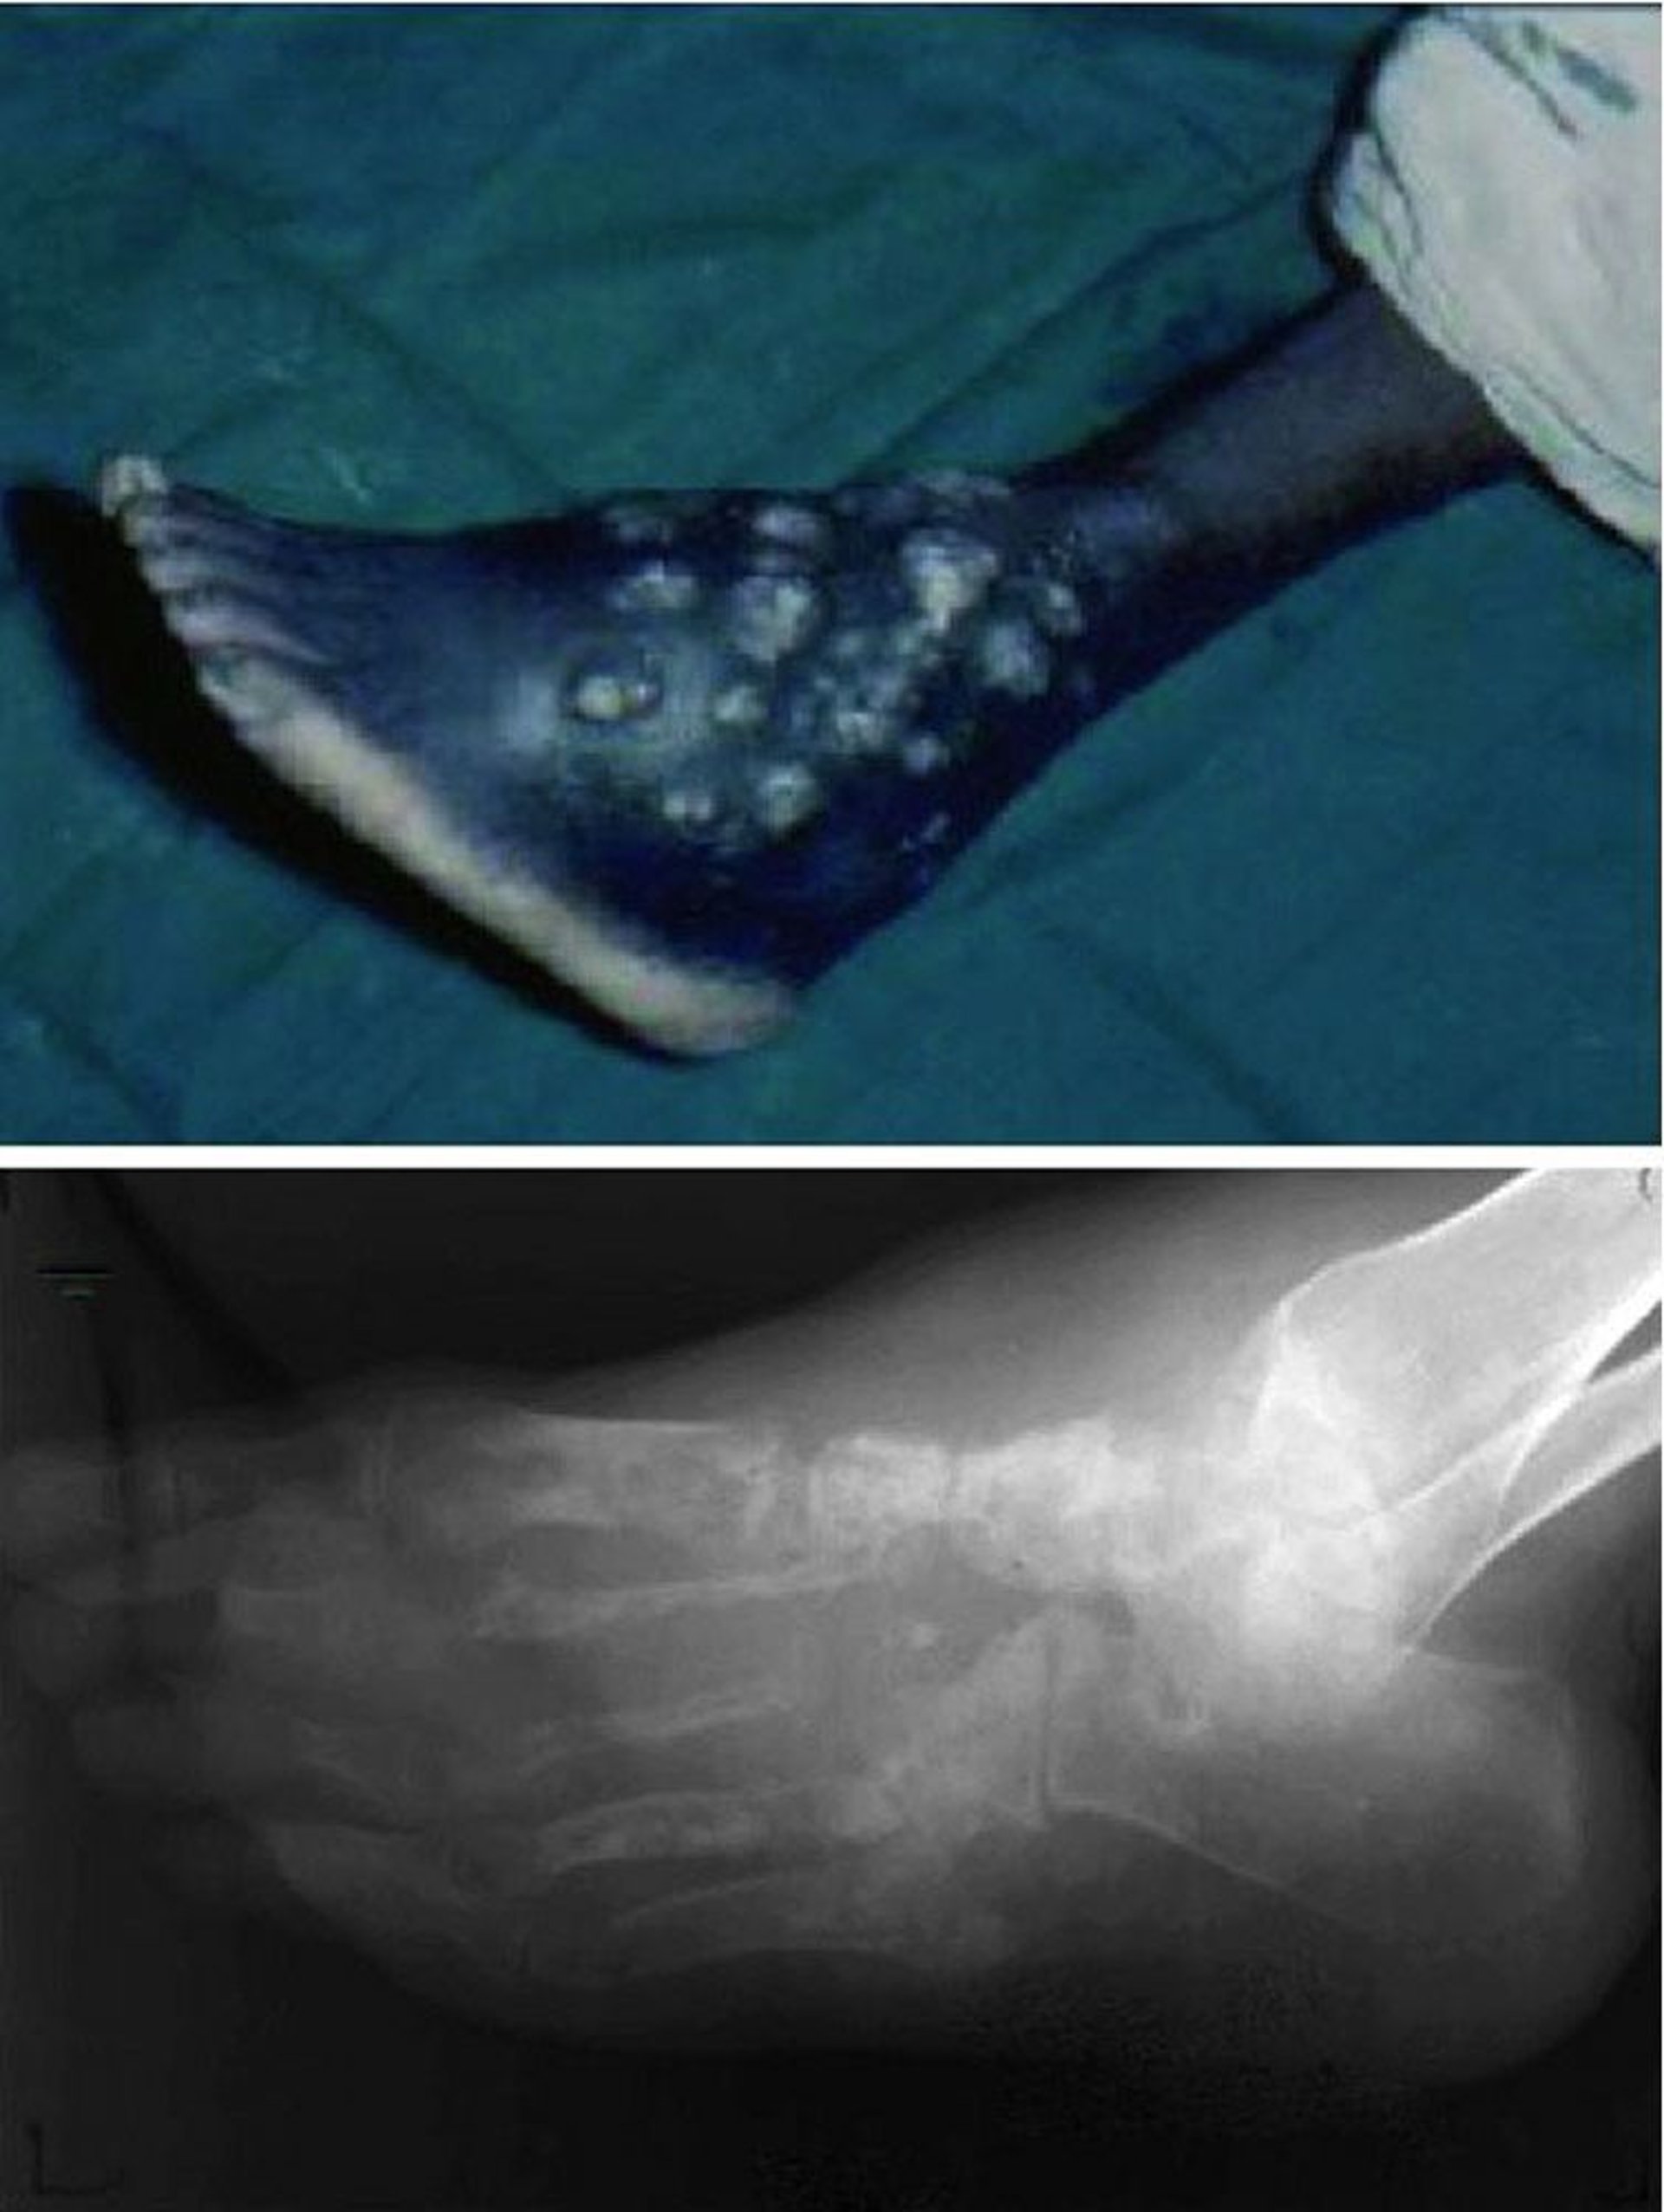

Micetoma (Pie de Madura)

Esta fotografia muestra heridas crónicas, que no curan, con episodios recurrentes de drenaje y ulceración (arriba), y la destrucción avanzada de la arquitectura ósea completa del pie (abajo).